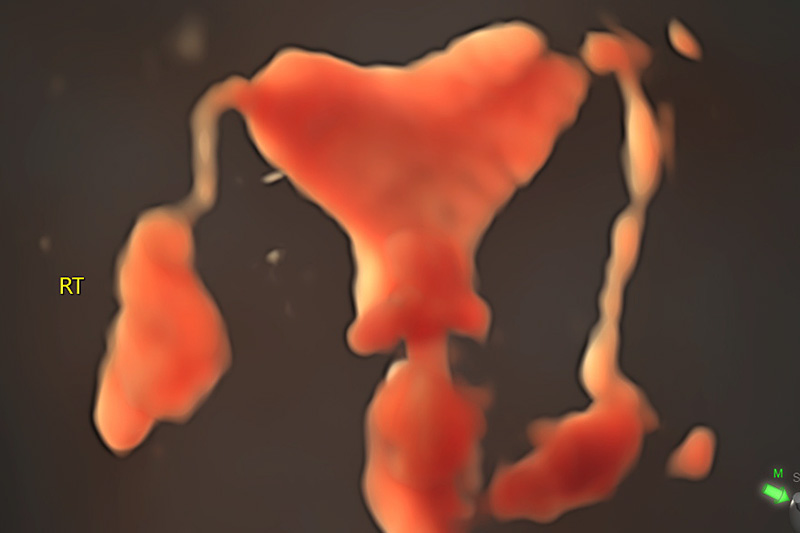

【超声造影实时成像】

子宫输卵管超声造影是观察和评估输卵管通畅度的一种检查方法。这种检查安全、无需麻醉、无创,是不孕不育诊疗过程中最常用的检查手段之一。医生向子宫腔内注入造影剂,通过超声检查实时动态成像,观察宫腔形态和输卵管走行。

因此,这个检查不仅能看到输卵管通不通,还能让整个宫腔充满液体,更清楚地看到宫腔内如息肉,粘膜下肌瘤,宫腔有无粘连、是否畸形。此外,还可以同时排除卵巢疾病等导致不孕的原因,进而诊断宫腔病变和判断输卵管通畅性。